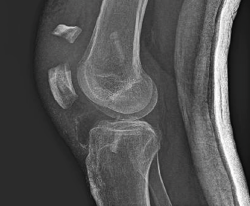

A las 2 semanas reinicia la fisioterapia. En septiembre de 2019, a los 2 meses de la cirugía, sufre una caída casual, presentando una fractura de la rótula derecha (Figura 3), por lo que se lleva a cabo una reducción abierta y osteosíntesis de la fractura en “T” de la rótula derecha. En la cirugía se realiza valoración artroscópica de la plastia del LCA, que se aprecia íntegra.

Figura 3. Imagen de la fractura de la rótula. Se aprecia la situación de las pastillas óseas en los túneles tibial y femoral.

La tercera fractura es una fractura de la rótula favorecida por la pérdida de la integridad de la cortical anterior y una posible osteopenia por la cirugía, que ha podido favorecer una disminución de la resistencia mecánica y facilitar la fractura con la caída. No podemos descartar, por la elevación del fragmento proximal, que junto a la contusión directa hubiese un componente de contracción contrariada del cuádriceps, como factor añadido a la etiopatogenia de esta fractura. En este caso, un correcto abordaje de esta ha permitido una solución adecuada con una correcta funcionalidad de la rodilla.